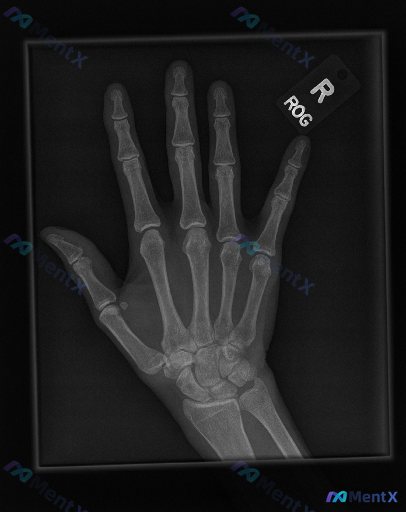

整理了一张右手正位X光片的完整影像分析资料,大家可以先看看关键表现: - 骨骼与关节:各指骨、掌骨、腕骨皮质连续,骨小梁规律,关节面光滑,关节间隙正常,解剖对位良好; - 骨质与软组织:整体骨密度无明显异常,无骨膜反应,周围软组织轮廓尚可; - 特殊发现:第一掌指关节掌侧可见一枚籽骨。 拿到这样的影...